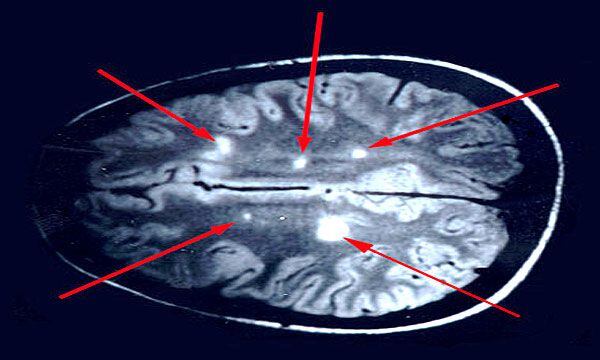

Investigadores de la Universidad de Oxford estudiaron los cambios que ocurrieron a nivel cerebral en 785 participantes en un gran estudio británico, y observaron “una mayor reducción en el grosor de la materia gris y el contraste de tejido en la corteza orbitofrontal y la circunvolución parahipocampal, mayores cambios en los marcadores de daño tisular en regiones conectadas funcionalmente con la corteza olfativa primaria, y mayor reducción en el tamaño global del cerebro. Los participantes infectados también mostraron, en promedio, un mayor deterioro cognitivo entre los dos puntos de tiempo”, tal como reportaron los investigadores en la publicación.

Para el trabajo, del que participaron personas entre de 51 y 81 años, los expertos tomaron imágenes cerebrales de los pacientes en dos oportunidades, incluidos 401 casos que dieron positivo por infección con SARS-CoV-2 entre sus dos escaneos, con 141 días en promedio separando su diagnóstico y el segundo escaneo y 384 controles. Y reconocieron la dificultad de no contar con datos de imágenes previas a la infección, lo cual “reduce la probabilidad de que los factores de riesgo preexistentes se malinterpreten como efectos de la enfermedad”.